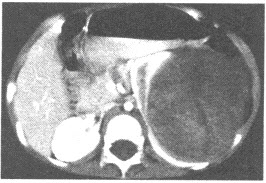

患者,男性,28岁,咳嗽咳痰1年余,CT检查如图所示。

(单选题)以下检查方法对诊断该病变最有价值的是()

A:主动脉造影

A:左肺下叶后底端紧贴膈面呈团块状阴影

B:边界一般较清晰,其长轴指向内后方,则指示与胸主动脉有联系

D:主动脉造影有助于确诊该疾病

E:CT增强扫描呈不均质强化,合并感染时可见气液平

F:MR多轴位扫描可现病灶内血管结构及静脉引流情况